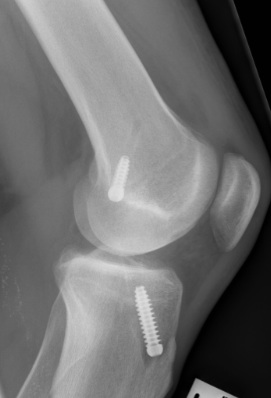

Uncertain if endobutton has flipped

- check with II

- cut down on lateral femoral cortex

- supplement with interference screw